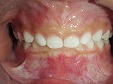

~術前~

オールセラミック修復

~術後~